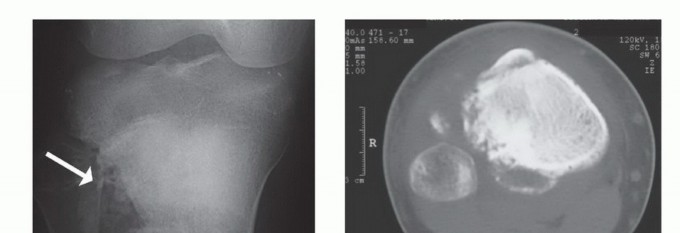

صورة شعاعية تظهر ساركوما عظمية في قصبة الساق القريبة لمريضة تبلغ من العمر 17 عاماً.

صورة شعاعية توضح ورماً عظمياً في قصبة الساق القريبة.

صورة شعاعية تظهر ورماً خلوياً عملاقاً في قصبة الساق القريبة.

صورة مقطعية توضح الورم الذي يملأ مشاش قصبة الساق القريبة.

صورة مقطعية أخرى للورم في قصبة الساق.

صورة شعاعية جانبية توضح ساركوما عظمية في قصبة الساق القريبة.

صورة شعاعية تظهر تدميراً قشرياً وامتداداً للأنسجة الرخوة للورم.

صورة مقطعية توضح تدميراً قشرياً وامتداداً للأنسجة الرخوة للورم.